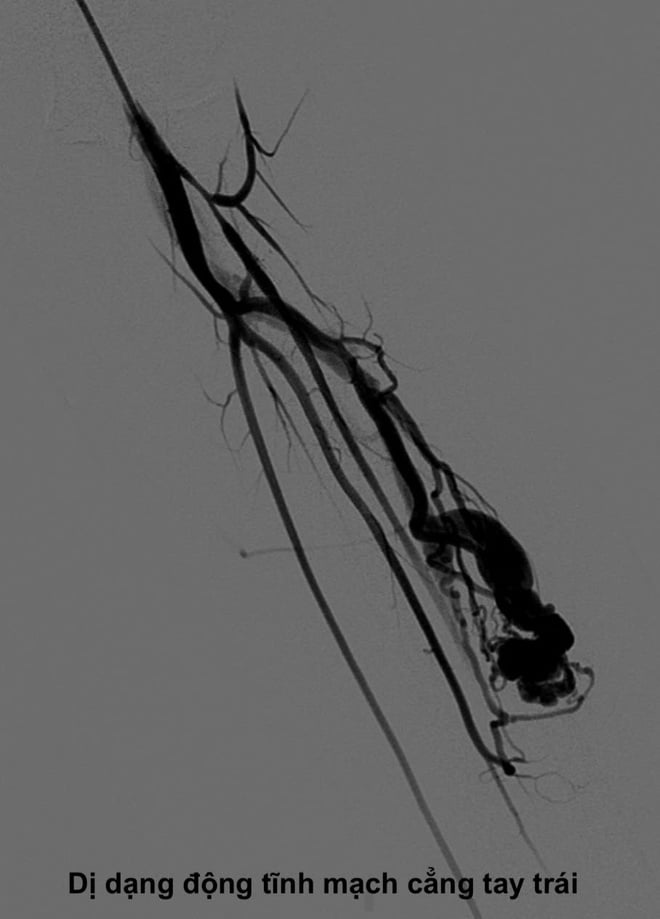

នៅនាយកដ្ឋានរូបភាពរោគវិនិច្ឆ័យ និងវិទ្យុសកម្មអន្តរកម្ម (មន្ទីរពេទ្យសាកលវិទ្យាល័យវេជ្ជសាស្ត្រហាណូយ) អ្នកជំងឺត្រូវបានពិនិត្យយ៉ាងហ្មត់ចត់ និងអនុវត្តបច្ចេកទេសរោគវិនិច្ឆ័យឯកទេសដូចជា អ៊ុលត្រាសោននៃសរសៃឈាមវ៉ែន និងរូបភាពម៉ាញេទិក (MRI)។ លទ្ធផលបានកំណត់យ៉ាងត្រឹមត្រូវនូវដំបៅនេះថាជាការខូចទ្រង់ទ្រាយសរសៃឈាម (AVM) ដែលមានទីតាំងជ្រៅក្នុងសាច់ដុំកំភួនដៃឆ្វេង។

យោងតាមលោកវេជ្ជបណ្ឌិត ង្វៀន ង៉ុកគឿង (Nguyen Ngoc Cuong) ប្រធាននាយកដ្ឋានវិទ្យុសកម្មអន្តរកម្ម (មជ្ឈមណ្ឌលសម្រាប់រូបភាពរោគវិនិច្ឆ័យ និងវិទ្យុសកម្មអន្តរកម្ម មន្ទីរពេទ្យសាកលវិទ្យាល័យវេជ្ជសាស្ត្រហាណូយ) ការខូចទ្រង់ទ្រាយសរសៃឈាមគឺជាភាពមិនប្រក្រតីនៃសរសៃឈាមពីកំណើតដែលបង្កើតនៅក្នុងអំប្រ៊ីយ៉ុង ហើយកម្រមានណាស់។

ជាធម្មតា ឈាមចេញពីសរសៃឈាមនឹងឆ្លងកាត់បណ្តាញក្រាស់នៃ capillaries ដើម្បីផ្លាស់ប្តូរសារធាតុចិញ្ចឹមជាលិកា ហើយបន្ទាប់មកត្រឡប់ទៅសរសៃឈាមវ៉ែនវិញ។ ប៉ុន្តែនៅក្នុង AVM មាន "ផ្លូវកាត់" មិនធម្មតា។ ឈាមនឹងហូរដោយផ្ទាល់ពីសរសៃឈាមទៅសរសៃឈាមវ៉ែនដោយមិនឆ្លងកាត់បណ្តាញ capillary ។

លោកវេជ្ជបណ្ឌិត Cuong បានពន្យល់ថា លំហូរឈាមដែលមានល្បឿនលឿនដែលឆ្លងកាត់ការខូចទ្រង់ទ្រាយនេះនឹងមិនអាចផ្តល់អុកស៊ីហ្សែន និងសារធាតុចិញ្ចឹមដល់ជាលិកានៅខាងក្រោមចរន្តបានទាន់ពេលវេលានោះទេ។ នេះនាំឱ្យមាន "បាតុភូតលួច" ដែលក្នុងនោះការខូចទ្រង់ទ្រាយបូមឈាមពីសរសៃឈាមធម្មតាដែលនៅក្បែរនោះធ្វើឱ្យម្រាមដៃឬអវយវៈទទួលរងនូវជំងឺ ischemia រ៉ាំរ៉ៃ។ នេះគឺជាមូលហេតុនៃរោគសញ្ញានៃការឈឺចាប់ ស្ពឹក ហើម កំដៅ ឬសូម្បីតែការខូចទ្រង់ទ្រាយនៃអវយវៈរបស់អ្នកជំងឺ។